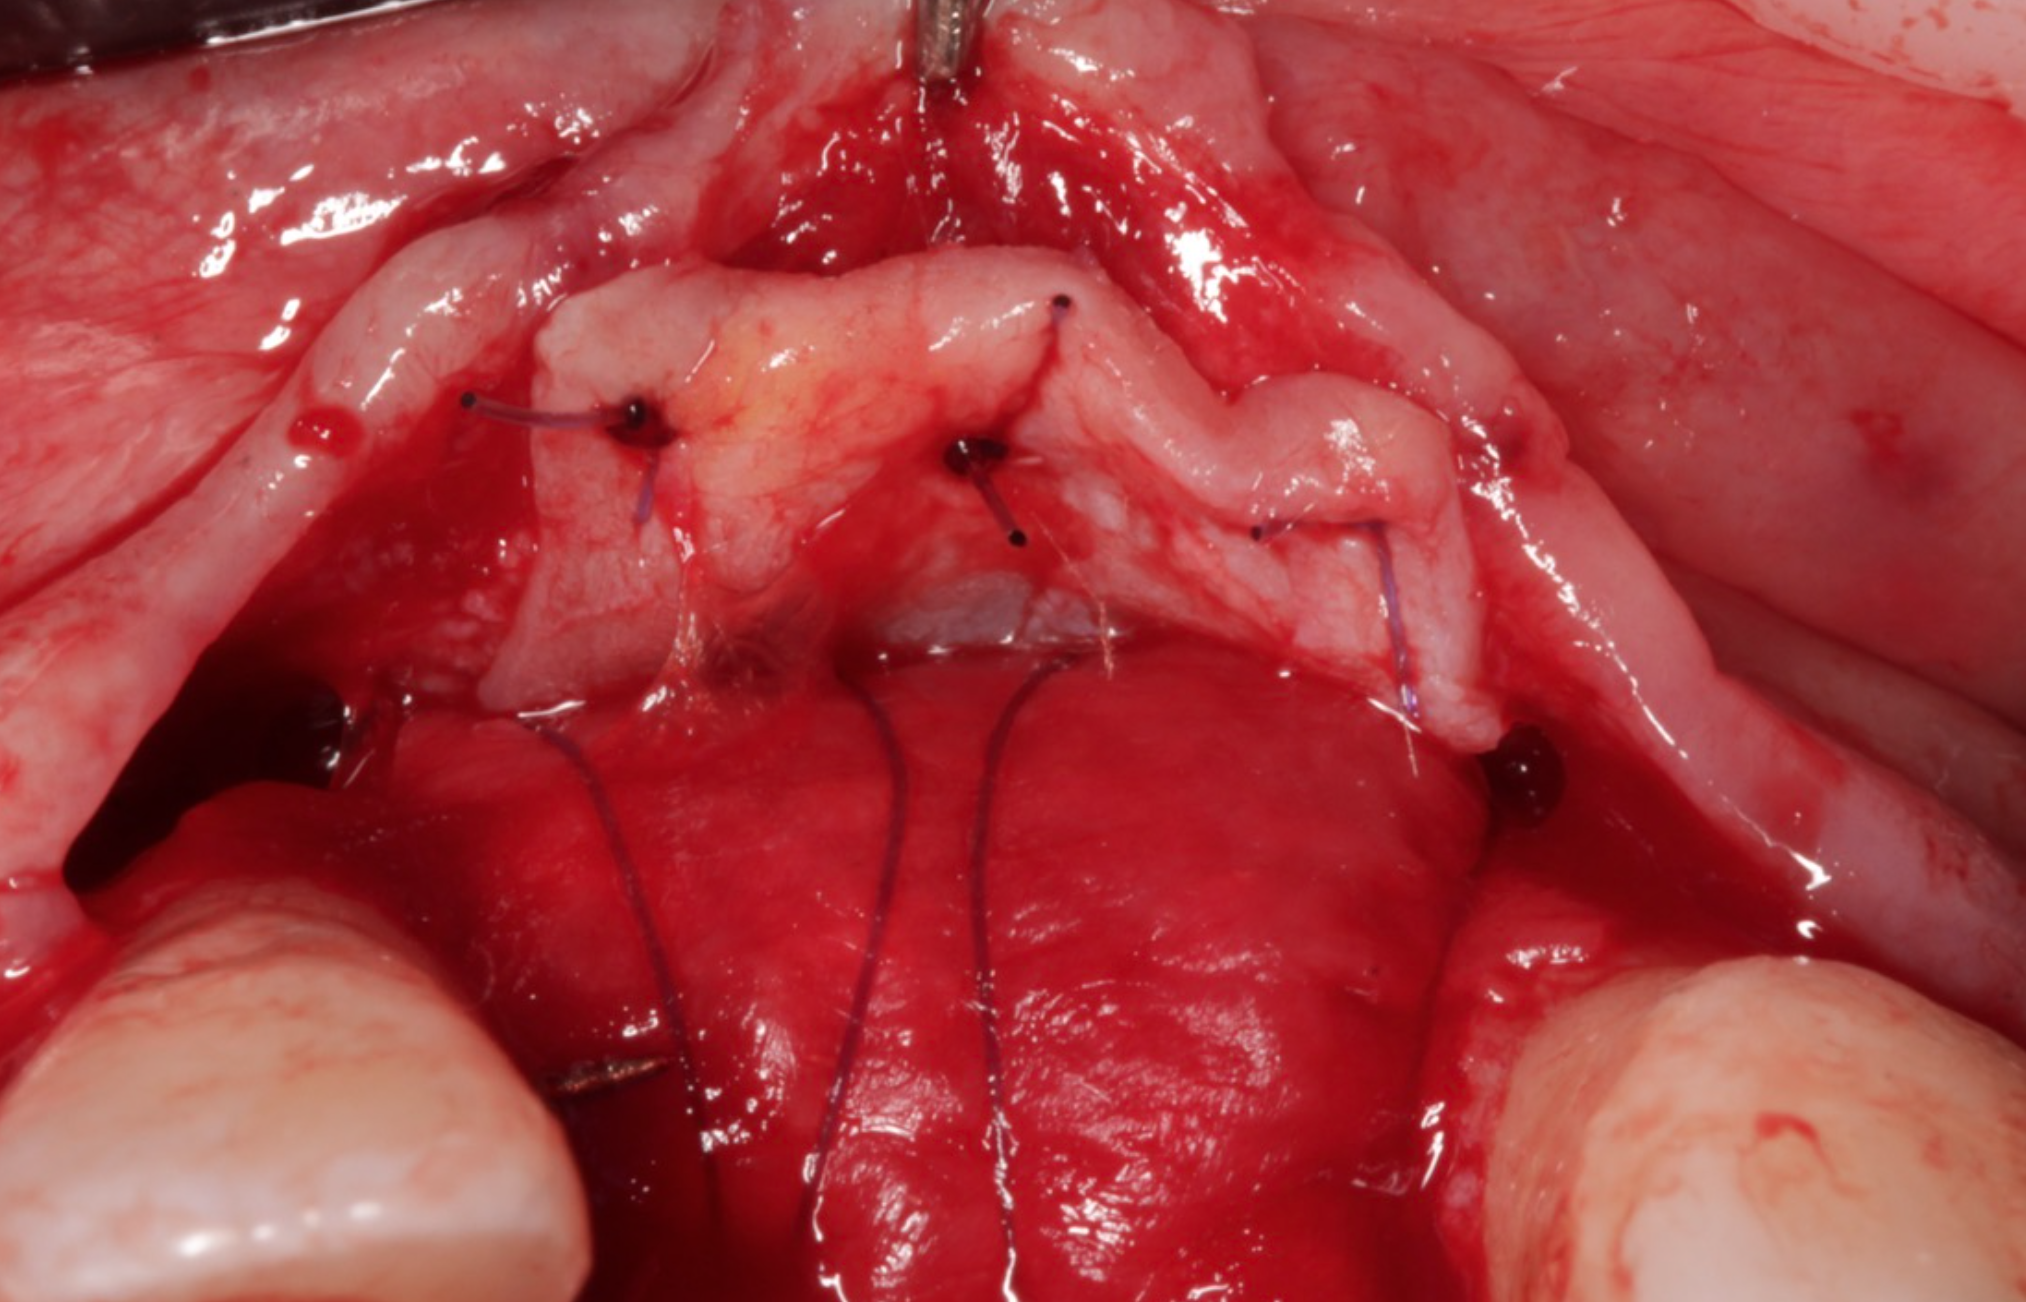

To address this, Dr. Nik employed the Sausage Technique, as described by Dr. Istvan Urban, for effective bone regeneration. During the first stage, bone augmentation was performed using a Ti-reinforced, non-resorbable dense PTFE membrane, combined with a mixture of autogenous bone particles and Mineross allograft from Biohorizons Camlog UK. After 7 months of smooth and successful healing, Dr. Nik placed a Conelog Progressive implant, supplemented by additional bone grafting with a resorbable striate and collagen membrane using the Mini Sausage Technique to ensure enhanced bone stability.

To optimise soft tissue support, Dr. Nik also performed a connective tissue graft from the palate for improved tissue thickness.

• Additional bone grafting and Connective Tissue Grafting